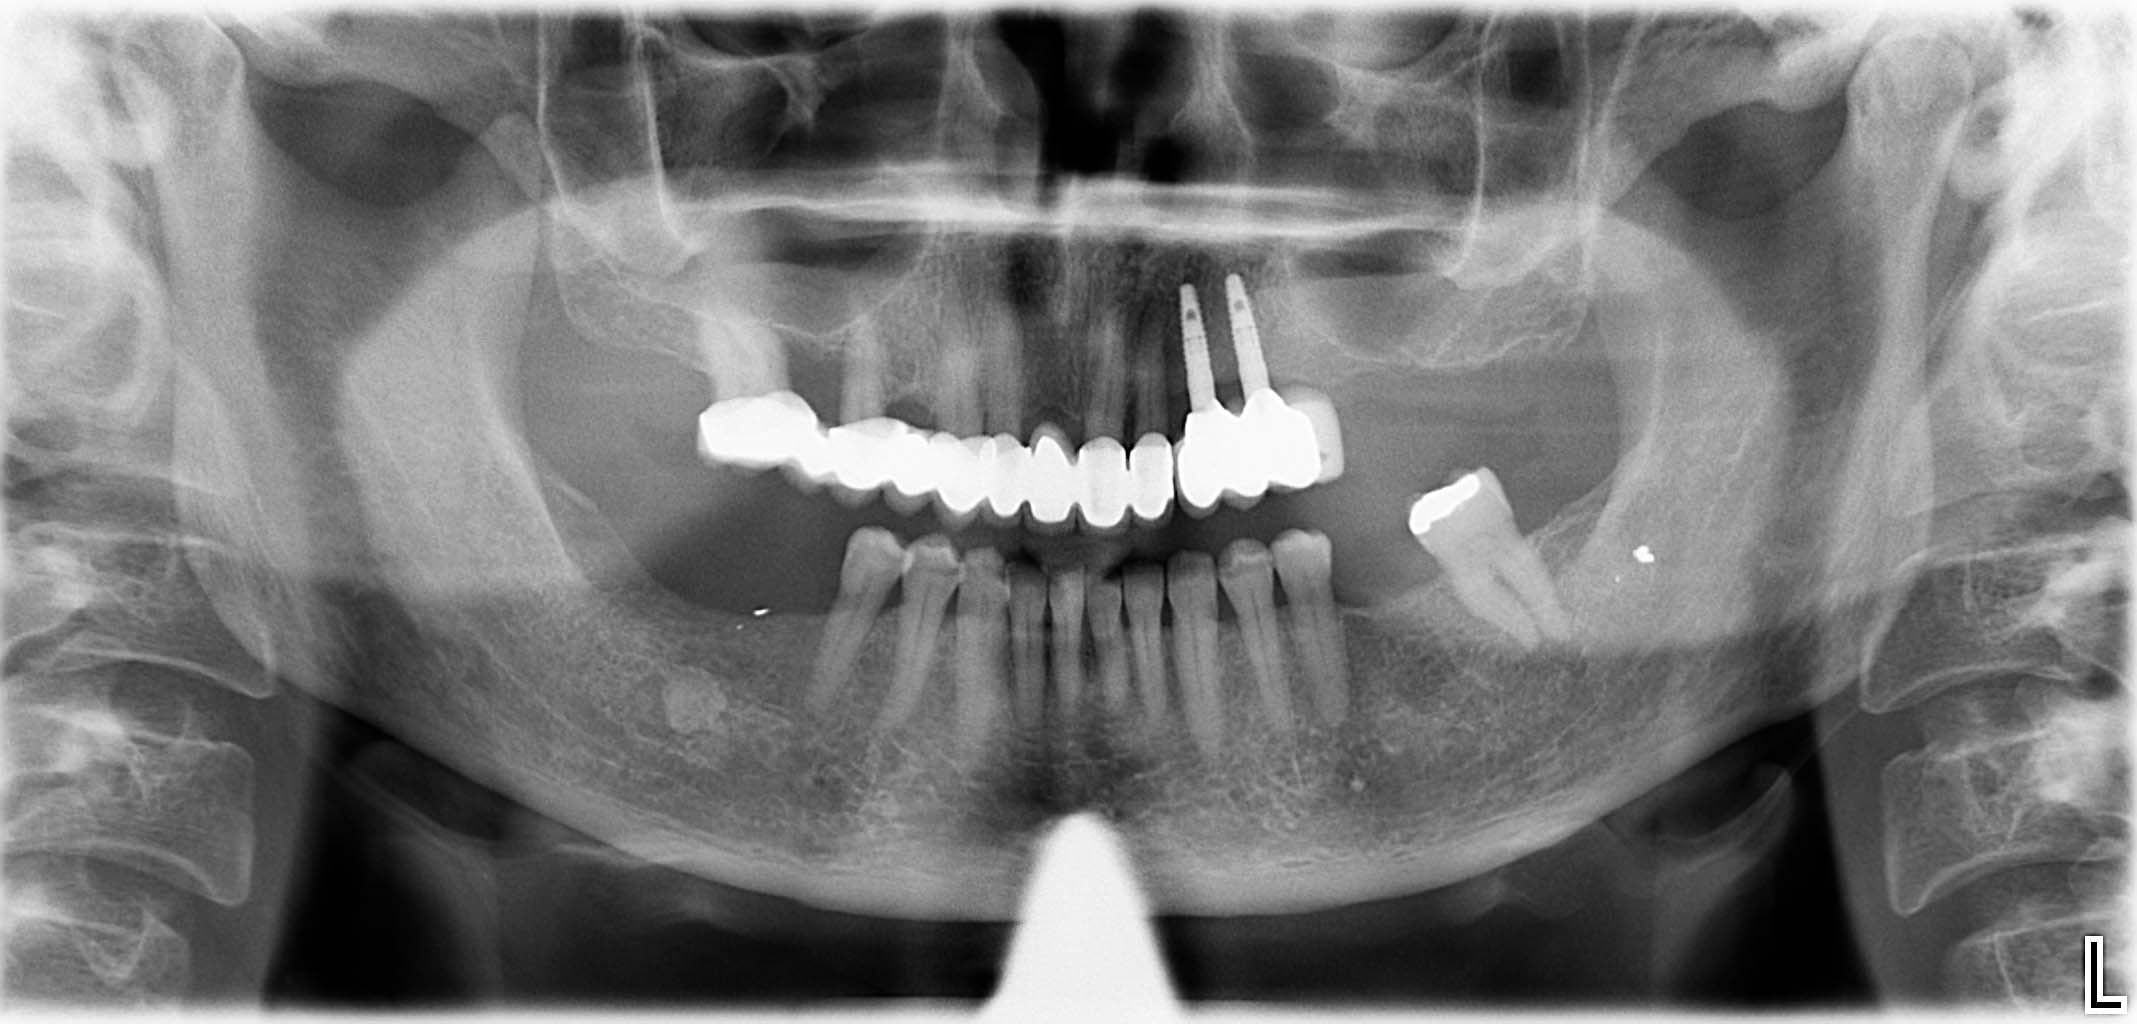

Erfolgreich implantierte Patientenfälle (klinische Fotos)